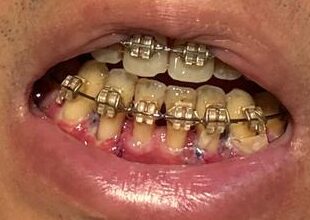

歯肉移植手術1回目(手術方式:CBCT、術部:左下2番・3番、手術時間1.5時間)

・3時間後:術部(下部のみ、上部は違和感のみ)と頭の痛みが始まった。すぐお風呂に入り、おかゆを少量食べて薬を飲み、すぐに寝た。

・7時間後:仮眠から起きると、唾液に血が常に混じり、少量の出血がずっと続いていた。この日は歯磨きできなかった。

・17時間後:翌朝目覚めると出血は止まっていて、術部の痛みは減った。体調もかなり良い感じだった。歯磨きはゆっくりすればできた。食事は難しいので右側(術部でない側)で時間をかけて食べた。

・27時間後:体のほてりを感じ始めた。1日1回飲む薬の効果が切れてきているようで、食事を取った後すぐに薬を飲んだら落ち着いた。

・51時間後:前日同様に体のほてりを感じ始めた。ただし昨日よりも楽で良くなってきているのを実感した。薬は3日分飲み終わったので終了。

・~6日後:その後は特に支障なく仕事もできた。食事や歯磨きは痛みがあり、慎重にゆっくりと。

・7日後:歯茎の状態確認で朝から検診予定。朝の歯磨き後から上顎の術部より出血が止まらなくなった。歯ブラシが当たってしまったようだ。歯磨きから歯医者までの2時間ほど常に血がにじみ出てて怖かった。検診時に出血部を縫ってもらった。もともとブラッシングが強い過ぎる癖があるので、歯磨きは本当に慎重する必要があると感じた。また、下の術部も歯磨きの影響で縫っていた糸が一部取れたので再縫合してもらった。

・21日後:多少の歯茎の定着が見られたものの、想定より歯肉は戻らなかった。その後歯医者で状況を確認した結果、再度歯肉移植することになった。

・28日後:食事や歯磨きの際の上顎の違和感がようやくなくなってきた。時間が経つにつれ、下の術部より上顎の歯肉採取部の方の痛み、違和感が大きかったので、それが1ヶ月ほどでようやく収まってきた。

左(上)から:術後5時間後、術後17時間後、術後1週間後、術後3週間後